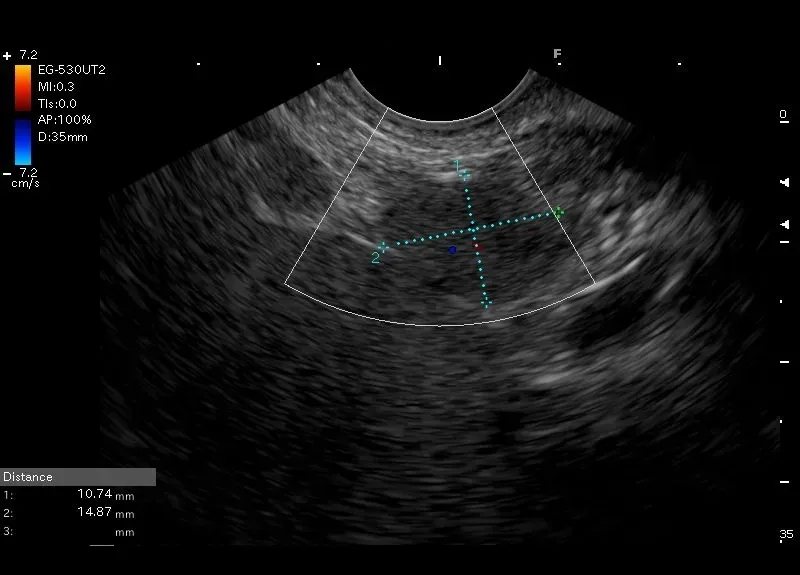

Owalna zmiana wielkości około 11/15 mm o echogeniczności i strukturze zbliżonej do położonej obok śledziony- śledziona dodatkowa